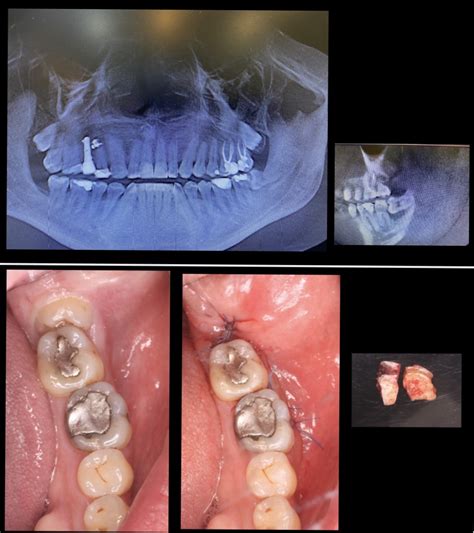

Primero, consulta a tu dentista para obtener un diagnóstico preciso. Esto generalmente incluye una radiografía panorámica para determinar la posición exacta de las muelas y evaluar la complejidad de la extracción.

Evaluación preoperatoria

El proceso para ser retiradas puede variar, ya que cada muela es única y de ellas dependerá el procedimiento. La duración de esta cirugía también depende de su estado, de ahí la importancia de asistir a una evaluación preoperatoria.

Tipos de extracción

En la mayoría de los casos es más fácil extraer las muelas de juicio superiores que las inferiores. La extracción de muelas de juicio no impactadas es más simple y la opción estándard. Se opta por esta cuando las muelas ya han erupcionado y son visibles en la encía.

Los casos más complicados se dan cuando es necesaria una extracción parcial por muela impactada, es decir, que el diente sigue incrustado en la mandíbula de forma parcial. También puede ser completa o total por impacto óseo, que es cuando el diente está completamente atascado en la mandíbula y no ha erupcionado.

Procedimiento

El procedimiento toma alrededor de 45 minutos y generalmente puede hacerse en el consultorio odontológico. Los pasos son los siguientes:

- El dentista realizará una incisión en el tejido de la encía para acceder a la muela y el hueso.

- Posteriormente, elimina el hueso que impide llegar hasta la raíz y de ser necesario empieza a dividir la muela por secciones porque así resulta más sencillo retirarla.

- Una vez que haya retirado todos los pedazos de muela y limpiado el área, cose la herida mediante algunos puntos de sutura.

- Colocará un poco de gasa para controlar el sangrado y permitir que se cree un coágulo sanguíneo.

Posterior a la operación, luego de un período de recuperación de pocos días, tal vez debas acudir al especialista para que retire los puntos de sutura. Aunque hoy en día utilizan técnicas y materiales que permiten que el cuerpo los absorba. Incluso en ocasiones no es necesario hacer ningún tipo de sutura.